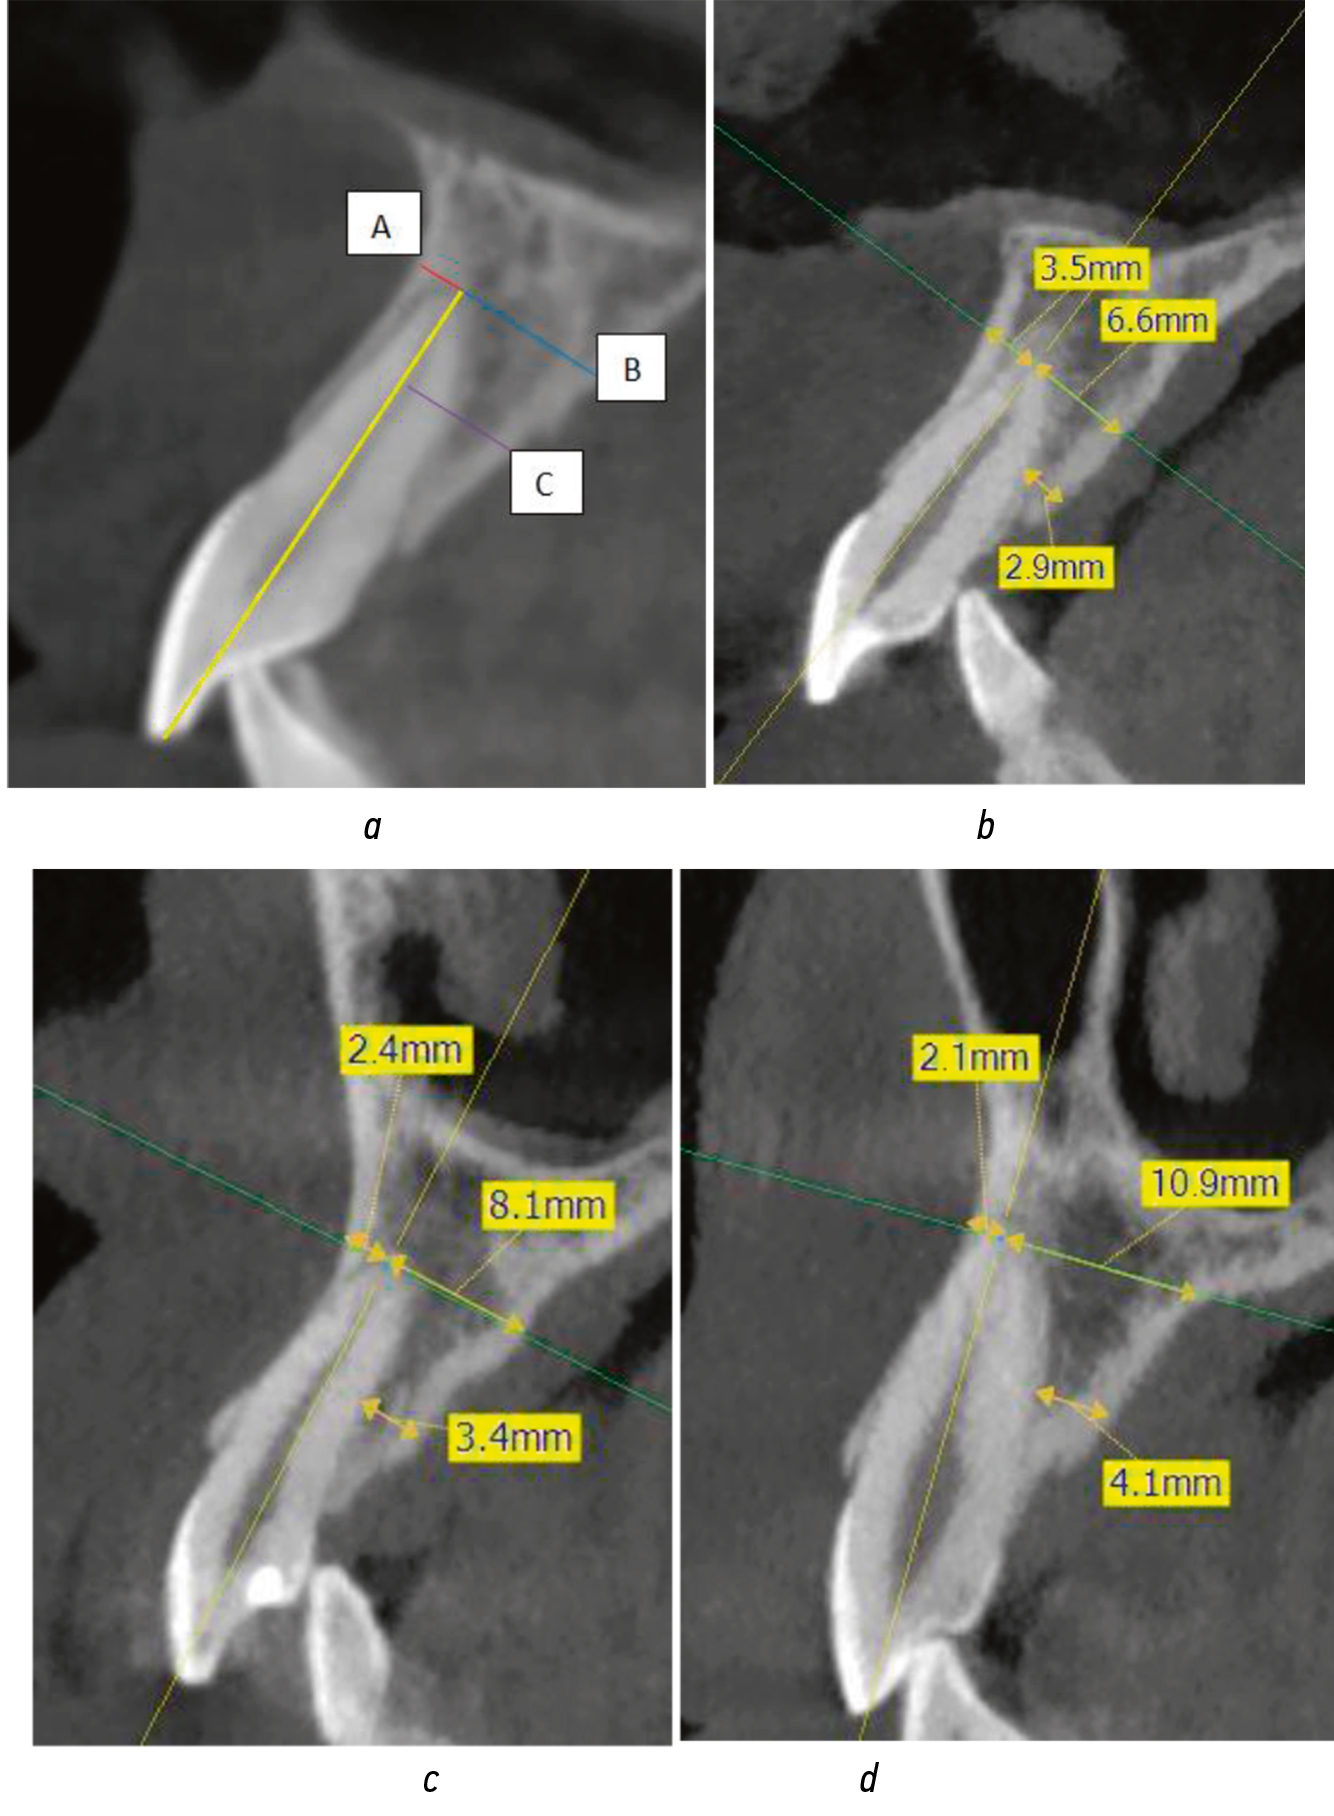

Bone thickness of the six anterior maxillary teeth was evaluated (Fig. 2a). Bone thickness on the vestibular side was measured as the distance from the perpendicular (tooth axis defined by 2 points along the canal) to the vestibular surface at the level of the apex (Fig. 2a, distance A). On the palatal side, it was measured as the distance from the perpendicular (tooth axis defined by 2 points along the canal) to the palatal surface at the level of the apex (Fig. 2a, distance B). Moreover, palatal bone thickness was measured as half the distance from the apex to the tooth axis at the level of the periosteum on the palatal side (Fig. 2a, distance C). The measurements were significantly different in the regions of the central and lateral incisors and the canines (Fig. 2b, c, d).

Fig. 2. Control measurements from cone-beam computed tomography images (sagittal sections) of the anterior teeth region: (a) standard dimensions; (b) tooth 1.1 region; (c) tooth 1.2 region; (d) tooth 1.3 region

Рис. 2. Контрольные измерения по изображениям конусно-лучевой компьютерной томографии (сагиттальные срезы) в области фронтальных зубов: а — типоразмеры; b — область зуба 1.1; с — область зуба 1.2; d — область зуба 1.3